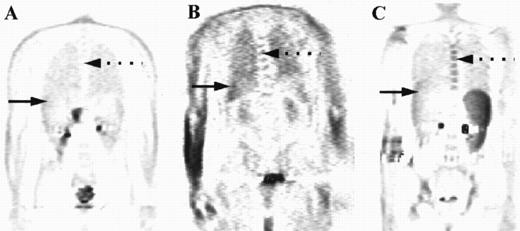

Coronal images are shown from three patients with different degrees of marrow uptake on PET. FDG uptake within the marrow is seen on these sections in the thoracic spine (broken arrows) and within the liver (solid arrow). The intensity of uptake was graded as less than liver (A), equal to liver (B), or greater than liver (C), with the marrow deemed to be abnormal where uptake was equal to or greater than liver.